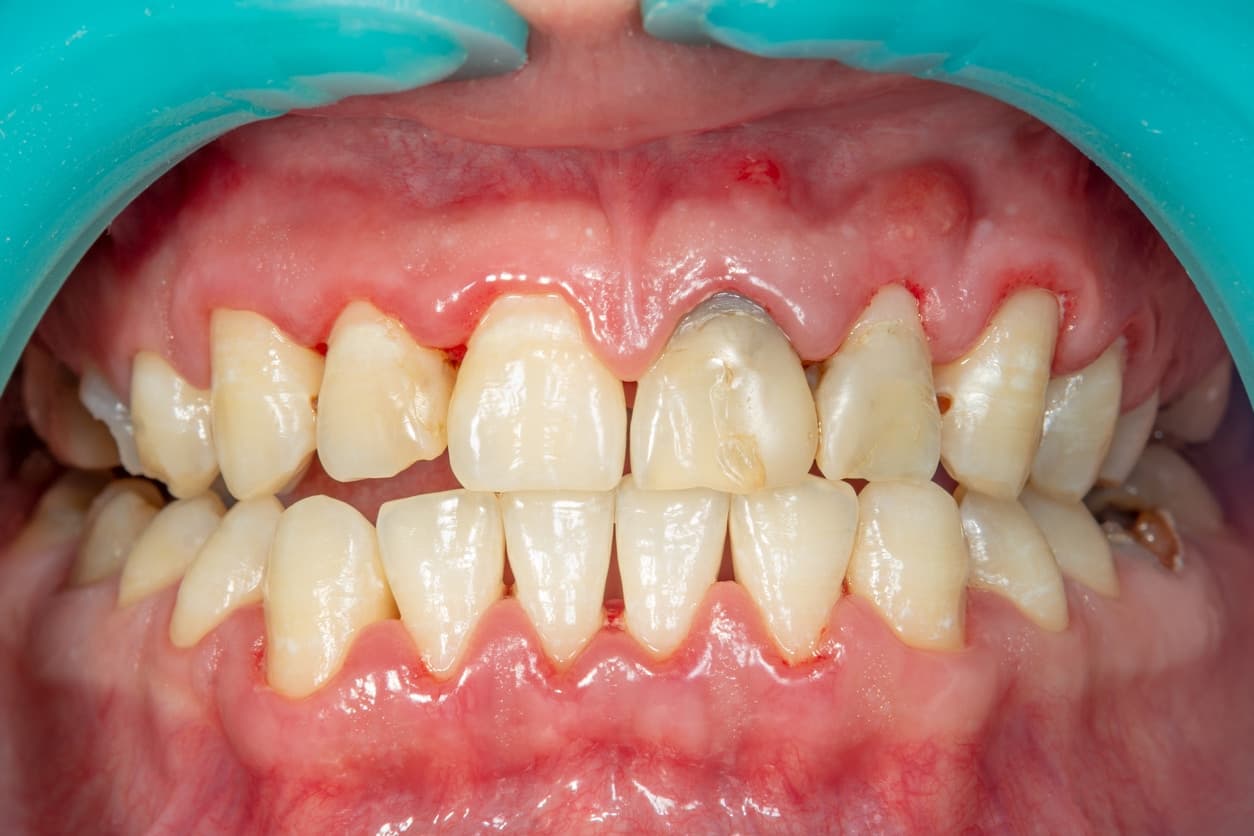

Periodontal diseases produce a range of oral signs that reflect progression from reversible gingival inflammation to destructive periodontitis with loss of supporting tissues.

Early and common symptoms include gum redness, swelling, and bleeding on brushing or flossing, which often signal gingivitis and can be reversed with improved hygiene and professional cleaning.

Gum recession and the appearance of longer teeth occur when the gingival margin migrates apically, exposing root surfaces and increasing sensitivity to hot, cold, or sweet stimuli; this can also create esthetic concerns and root caries risk.

Progressive periodontitis produces pocket formation, clinical attachment loss, and alveolar bone resorption, which manifest clinically as tooth mobility, drifting or changes in the way teeth fit together (bite changes), and difficulty chewing.